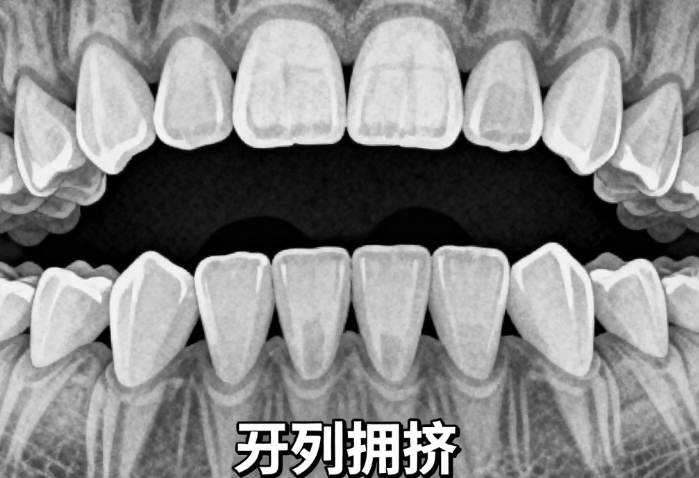

牙齒拔除矯正是常見的青少年地包天矯治方法之一。通過(guò)拔除部分牙齒,減少牙齒之間的擁擠,為調(diào)整牙齒位置和關(guān)系創(chuàng)造空間。這種矯正方法適用于輕、中度地包天病例,且非常經(jīng)濟(jì)實(shí)惠。